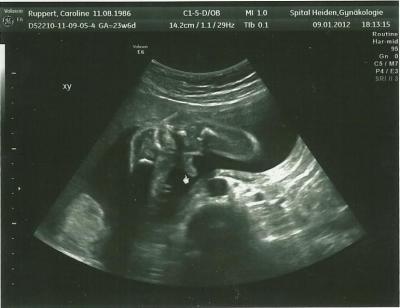

Hallo ihr lieben mitkugelnden es war heute so toll beim baby tv über 1 stunde wurde geschallt und es ist alles dran und am richtigen platz und das beste ist wir haben ein outing bekommen und zwar wird es ein RAPHAEL wir sind so happy er ist schon ca 660gr schwer und 30 cm groß leider haben wir heute kein schönes foto hin bekommen vom gesicht aber dafür das beweis foto

Bild zu Zurück von frauenarzt - Forum für Mai - Mamis